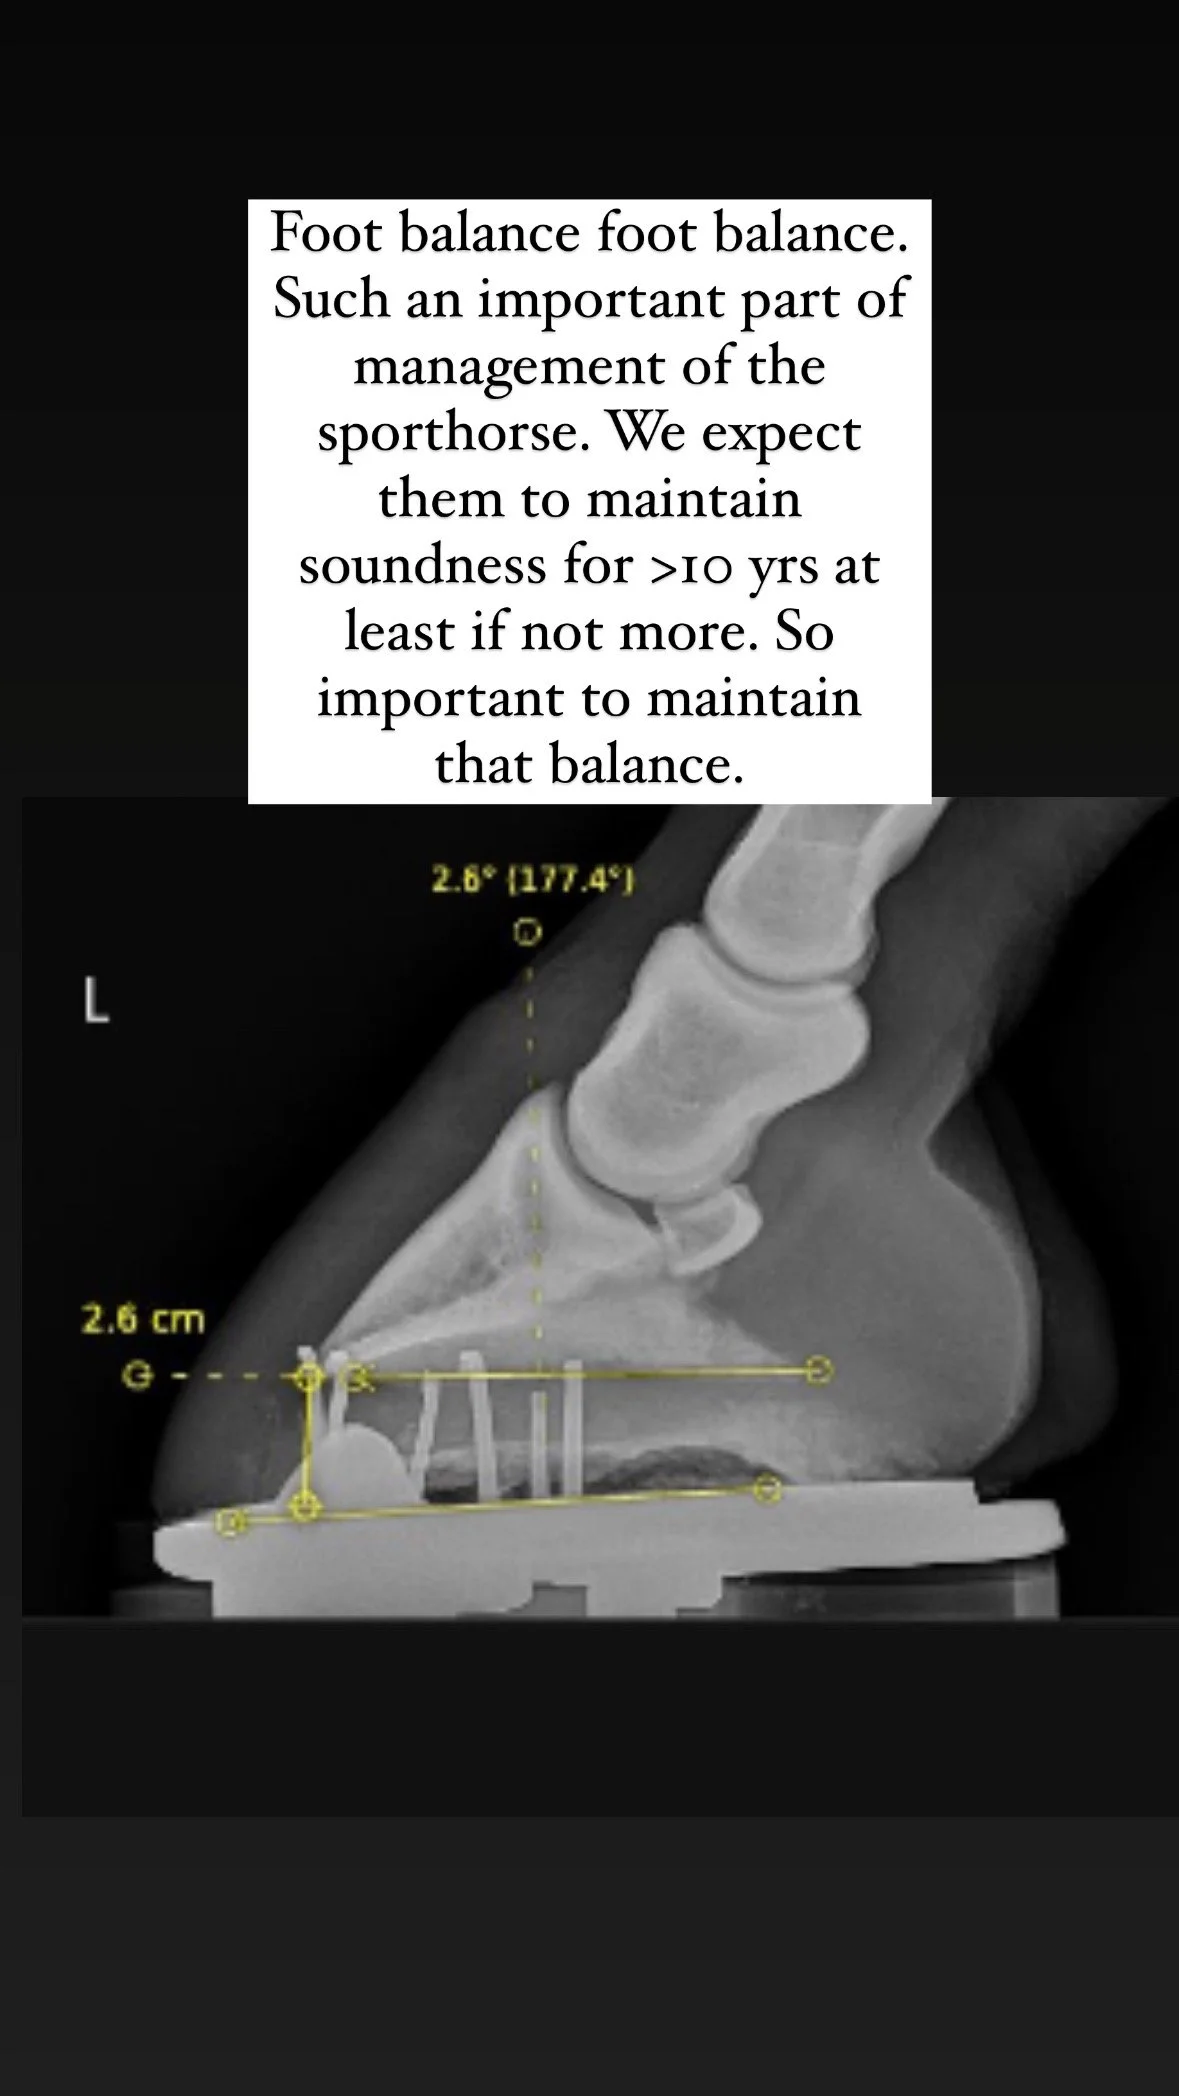

Maintaining correct hoof balance is essential for soundness, especially in performance horses, growing young stock, and horses recovering from injury.

Digital radiographs (X-rays) if required – to assess internal structures and alignment

X-ray guided feedback on hoof-pastern axis